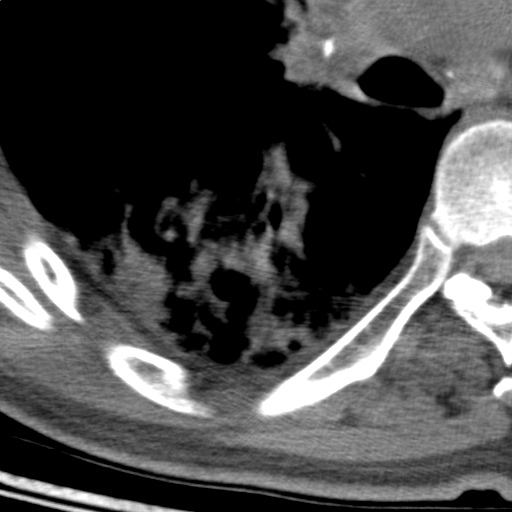

以下是引用随光逐影在2009-5-1 13:53:00的发言:[br]考虑为:1)两肺血行播散型肺结核;2)右肺下叶炎症感染。3)右侧胸膜增厚。